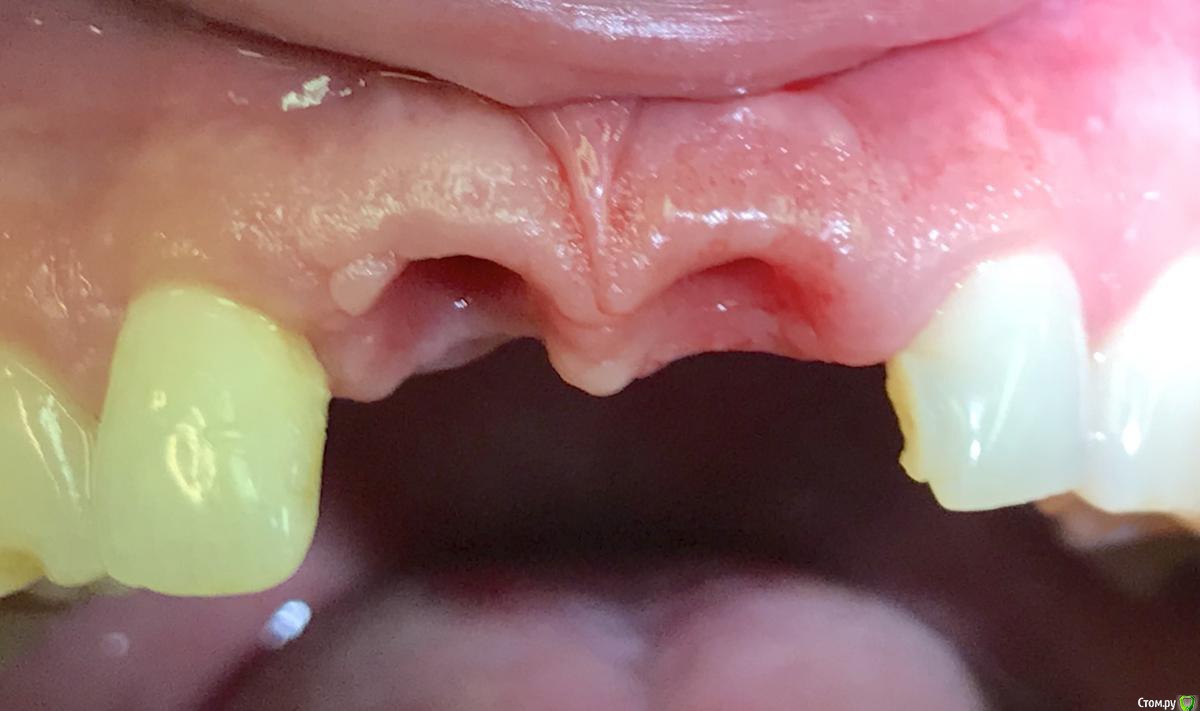

Astronaft Опубликовано 22 июня, 2018 Поделиться Опубликовано 22 июня, 2018 Коллеги, нужен ваш совет как поступить.Девушка, молодая, высокая улыбка , много десны видно.Появился свищь 5мм выше зенитов 11,12.11 - на удаление.http://miworks.weebly.com/uploads/1/6/8/7/16879370/untitled-1_1_orig.jpg http://miworks.weebly.com/uploads/1/6/8/7/16879370/x06408-1_orig.jpghttp://miworks.weebly.com/uploads/1/6/8/7/16879370/1_1_orig.jpg План: удалить, одномоментно имплант с времянкой, десну с бугра. БиоОсс вестибулярно.Мучает сомнение накрывать мембраной или нет. Если мембрана надо отслаиваться. А тут 12-11 сосочек только держится на связках. А если не накрывать чего ожидать?Делитесь мнением. Спасибо.Планируем повышать зениты, что бы как-то обыграть ситуацию.http://miworks.weebly.com/uploads/1/6/8/7/16879370/3_1_orig.jpg Ссылка на комментарий

колесников Опубликовано 22 июня, 2018 Поделиться Опубликовано 22 июня, 2018 Я бы внимание обратил не на костный пик а на вестибулярную пластинку и анатомию этого сегмента.Она уйдёт с корнем и далее у Вас (у пациента) от сосочка до грушевидного отверстия 2-3мм толщины. Если удалять целиком,то и нкрить по полной и отслаивать по самое немогу и далее все долго и нудно восстанавливать. Я бы удалял с выделением щита или как альтернатива IDR. Вероятно компактная пластинка анкилозировпна с корнем и экструзия может не пойти. 3 Ссылка на комментарий

Дмитрий Л. Опубликовано 24 июня, 2018 Поделиться Опубликовано 24 июня, 2018 Если кортикальная сохранится и вы в зазор между кортикалкой и имплантатом внесёте биоосс то смысл мембраны? Если графт будет контактировать вестибулярно со слизистой то лучше закрыть. По поводу главного вопроса. А вообще здесь толстый биотип и всё будет хорошо)Кстати вы планируете удалять сосудисто-нервный пучок или просто засверлитесь? И какой абатмент будете использовать? Ссылка на комментарий